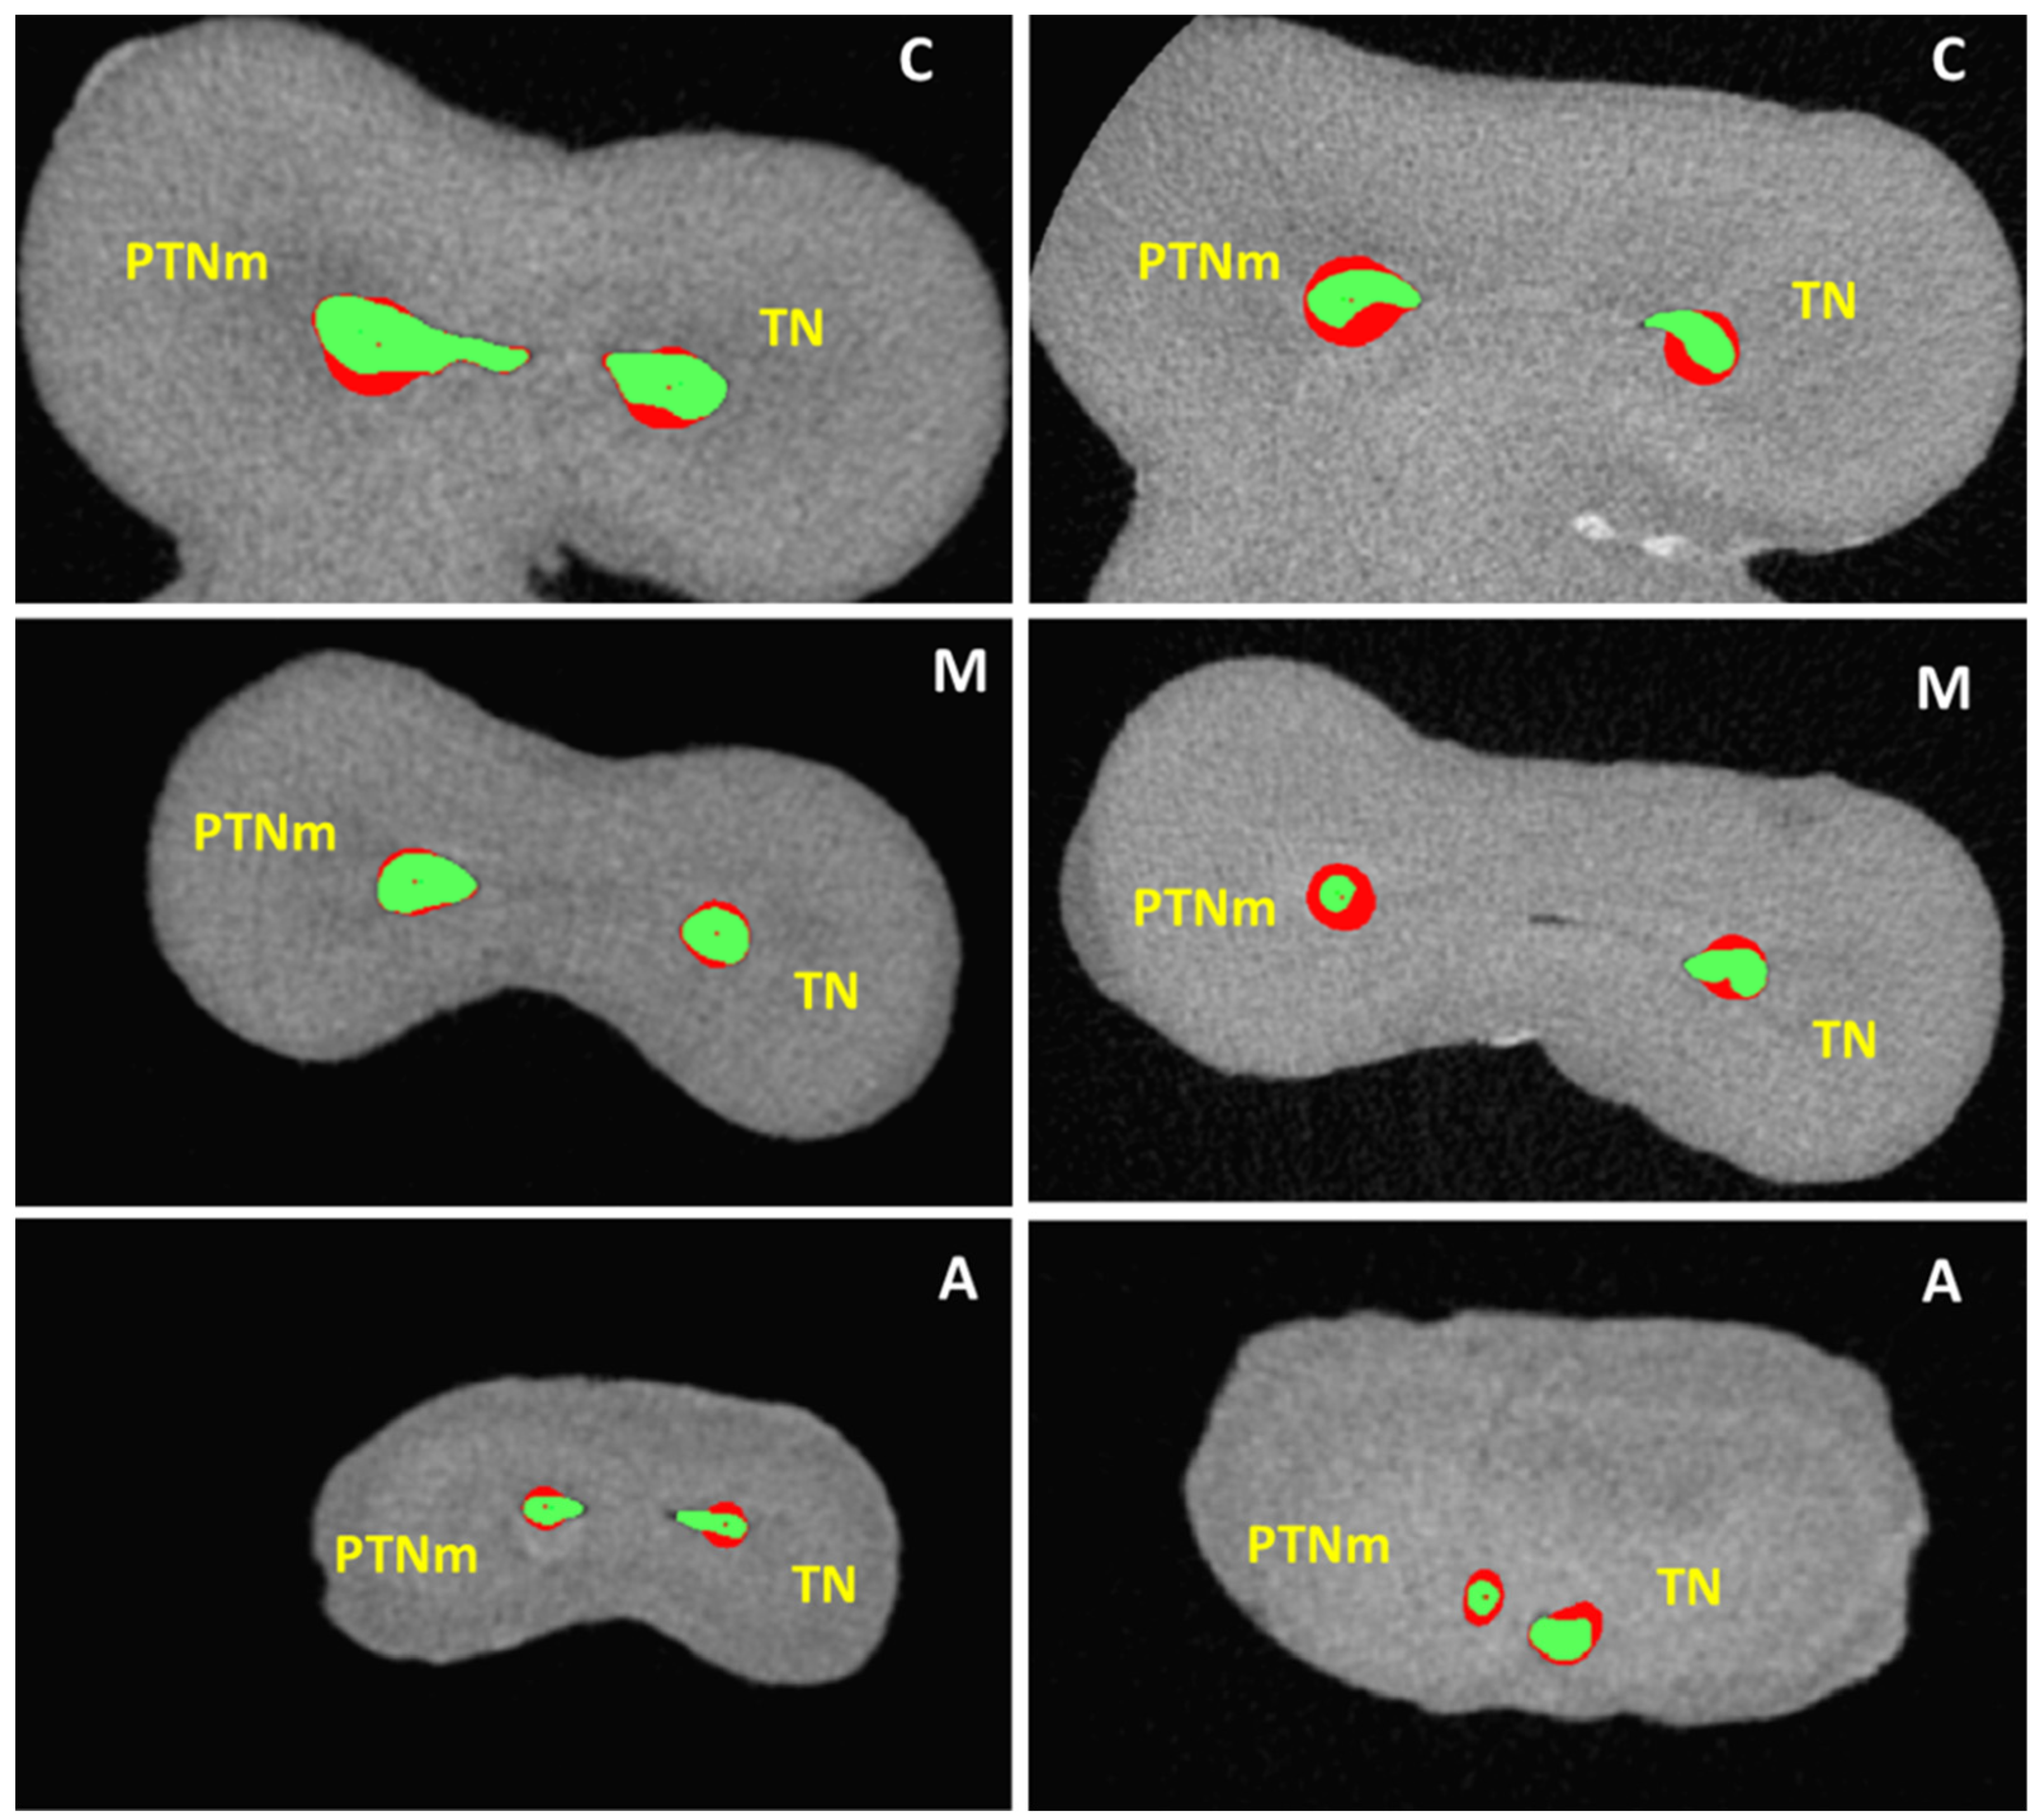

| Increase in Canal Volume (mm3) | Increase in Canal Surface Area (mm2) | Centroid Shift (mm−1) | RDR (Ratio) | RA (Ratio) | ||

|---|---|---|---|---|---|---|

| Group | Mean ± SD | Mean ± SD | Level of Analysis | Mean ± SD | Mean ± SD | Mean ± SD |

| Coronal | 1.25 ± 0.94 a | 0.60 ± 0.16 a | 1.82 ± 0.71 a | |||

| PTNm | 1.40 ± 0.80 a | 3.37 ± 2.17 a | Middle | 0.76 ± 0.47 a | 0.73 ± 0.18 a | 1.28 ± 0.22 a |

| Apical | 0.83 ± 0.45 a | 0.76 ± 0.21 a | 1.33 ± 0.36 a | |||

| Coronal | 0.77 ± 0.46 a | 0.61 ± 0.23 a | 1.30 ± 0.21 b | |||

| TN | 0.91 ± 0.44 a | 2.24 ± 1.48 a | Middle | 0.67 ± 0.29 a | 0.75 ± 0.14 a | 1.26 ± 0.16 a |

| Apical | 1.45 ± 0.27 a | 0.68 ± 0.26 a | 1.29 ± 0.22 a |